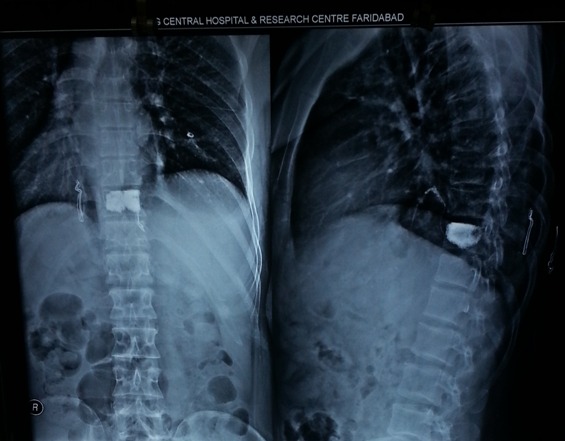

Scoliosis Patient before Surgery

Scoliosis Patient After Surgery